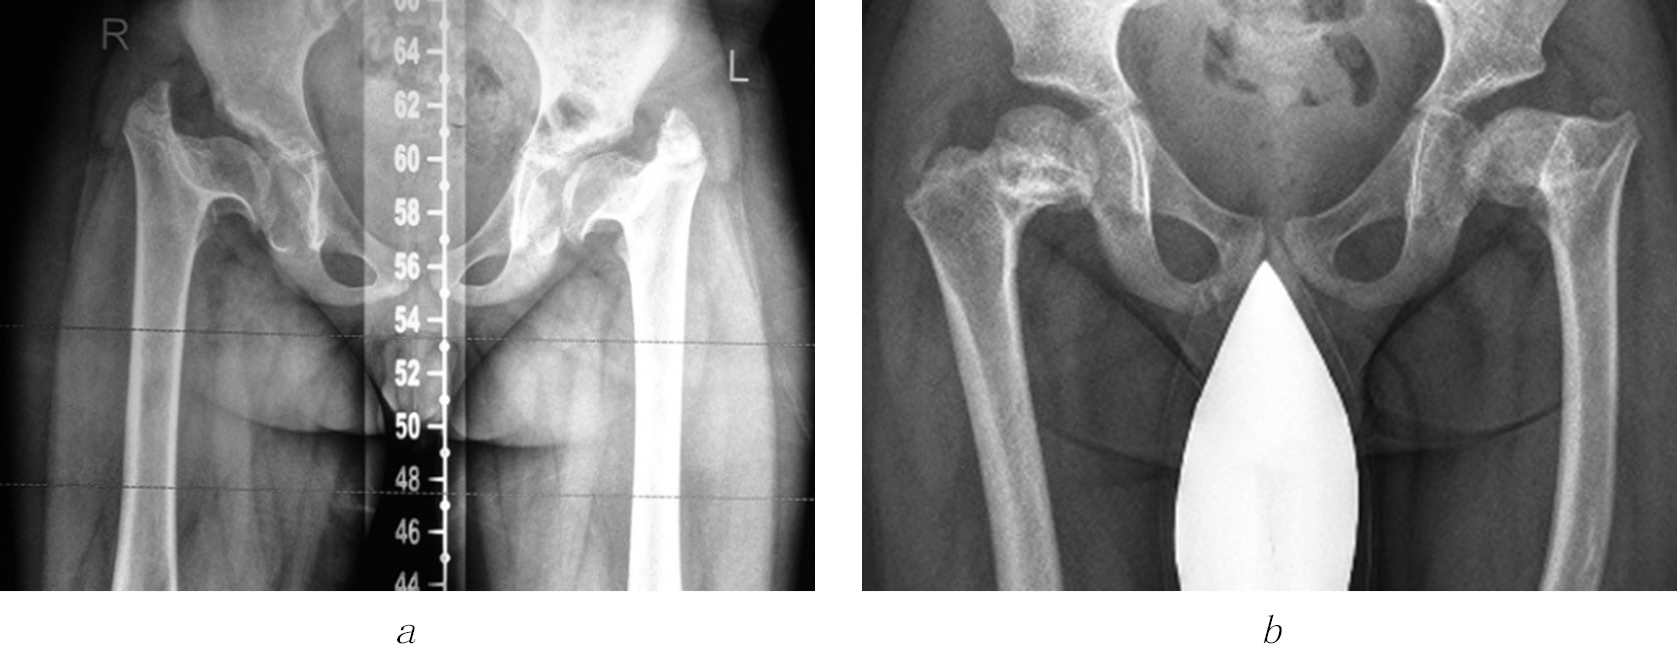

In four cases among those presented, the controlled growth technique was used to prevent the recurrence of deformity and correct the length of the fibula in dysfunction of the tibial growth zones (Fig. 6). After analyzing the literature data and own cases (recurrence of valgus deformity of the knee joint 2 and 4 years after corrective osteotomy of the femur and tibia), we concluded that temporary epiphysiodesis of the remaining functioning sections of growth zones is advisable. However, given the small number of cases, it is premature to evaluate the long-term results of temporary epiphysiodesis.

Fig. 6. Consistent application of controlled growth techniques (a) and compression-distraction osteosynthesis (b) to correct deformities of segments of the right lower limb